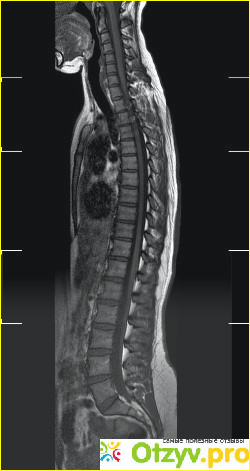

Правильнее будет сказать, МРТ позвоночника. Магнитно резонансная терапия, при котором исследуется позвоночный столб и окружающие его ткани. Действие на позвоночник производится с помощью электромагнитного поля.

Благодаря МРТ позвоночника специалист, который проводит данное исследование, может сделать заключение по поводу состояния мягких и костных тканей, а также видеть отображение позвонков, спинного мозга и межпозвоночных дисков. Исследование позвоночника посредством МРТ позволяет сделать более точное заключение по сравнению с другими методами его обследования. А значит, МРТ является более эффективным.